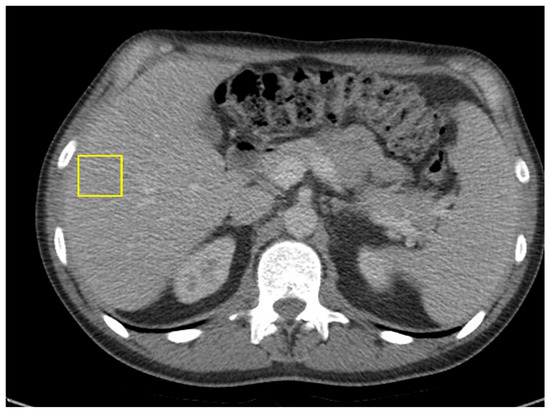

A 45-year-old male with a past medical history of lactose intolerance presented to his primary care physician with a five-week history of right lower-quadrant abdominal pain, bloating, swelling, discomfort, and increased flatulence. On physical examination, a visible and palpable mass was noted in the right lower quadrant. A contrast-enhanced computed tomography (CT) scan of the abdomen and pelvis revealed an 8 cm mass arising from the cecum, accompanied by presumed metastatic mesenteric lymphadenopathy and potential early invasion of the right lower-quadrant anterior abdominal wall musculature (Figure 1).

Figure 1. Mass with dimensions of 8 cm in cecum; presumed metastatic mesenteric lymphadenopathy with possibility of early invasion of RLQ anterior abdominal wall musculature.